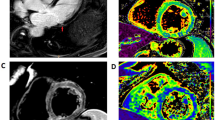

Vaccine-associated myocarditis. T2-weighted images (a) revealed the presence of myocardial edema located in the lateral wall of the left ventricle (arrowhead). A subepicardial LGE stria was evidenced on the same myocardial segments (b, white arrow). Those findings were confirmed by increased T1 (c) and T2 (d) mapping values on the lateral wall. At 117 days follow-up, CMR revealed a resolution of myocardial edema (e), with a reduction in LGE extension (f). Mapping sequences showed a decrease in T1 mapping values (g) and T2 values (h) that returned within the normal range